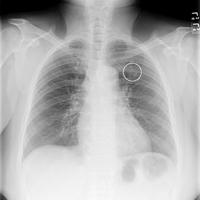

Chest X Ray For The Diagnosis Of Lung Cancer

Lung Cancer Pictures X Rays Of Tumors Screening Symptoms And More

Chest X Ray Diagnosing Lung Cancer Cancer Research Uk

Lung Cancer Radiology Case Radiopaedia Org

Left Lower Lobe Lung Cancer Radiology Case Radiopaedia Org